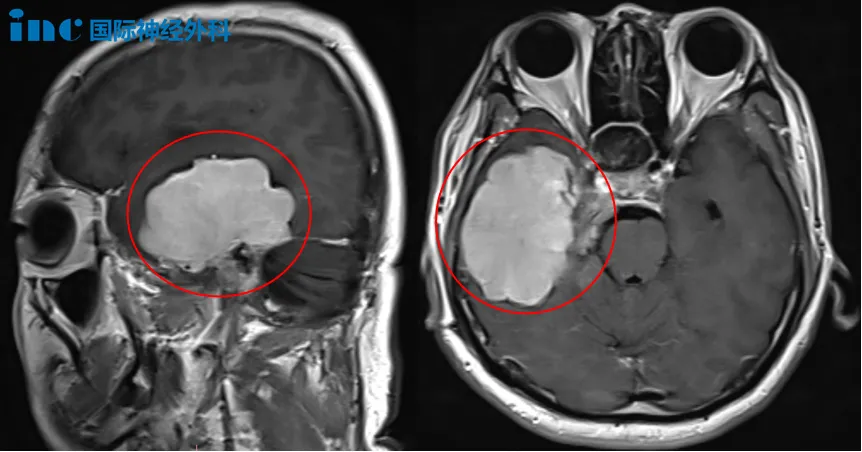

术前MRI

这台手术的挑战不仅在于肿瘤本身的复杂性,还源于患者曲折的治疗过程。在长达12年的漫长抗争中,林先生经历了一次开颅手术,两次伽马刀治疗以及中药治疗……然而首次术后出现面瘫,甚至右侧耳朵里长出奇怪“肿瘤”,切除后不幸失聪,这一切无疑是对其身心的严峻考验。然而这个狡猾的肿瘤依然不依不饶,疯狂生长,侵犯多个区域,甚至已经把三叉神经和滑车神经360°无死角的包裹。

面对这一复杂病情,林先生一家对本次手术充满期待,得知巴教授即将抵达天坛医院时,他们更是早早在国际部门外翘首以盼。林先生也始终保持着顽强的姿态以及决不放弃的精神。手术中,巴教授凭借精细操作将肿瘤完整剥离并实现满意切除。为预防脑嵴液漏,巴教授使用患者大腿部筋膜进行修补填充。今日恢复良好的林先生,妻子激动分享:“和10年前的那一次手术相比,这次术后状态好很多!”